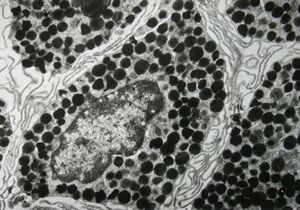

F, 7y. | molluscum contagiosum … virions